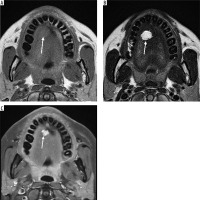

A 30-year-old male patient presented with painless swelling of the right parotid region. Coronal section of MRI shows a right parotid lymphoepithelial cyst. Cystic lesion with water content has low signal intensity on T1-weighted images, hence appears hypointense. In contrast, it has high signal intensity on T2-weighted images and has hyperintense appearance (Figures 4A-C).

Figure 4

Coronal section of MRI of parotid lymphoepithelial cyst. A) T1-weighted MRI image – note the hypointensity of the cyst on right parotid gland. B) T2-weighted MRI image – note the hyperintensity of the cyst. This classic signal pattern helps differentiate cystic lesions from other tumours, highlighting the importance of correlating imaging features with the clinical context for accurate diagnosis and treatment planning [Courtesy: Radiopaedia. DOI: https://doi.org/10.53347/rID-149218, rID:149218]